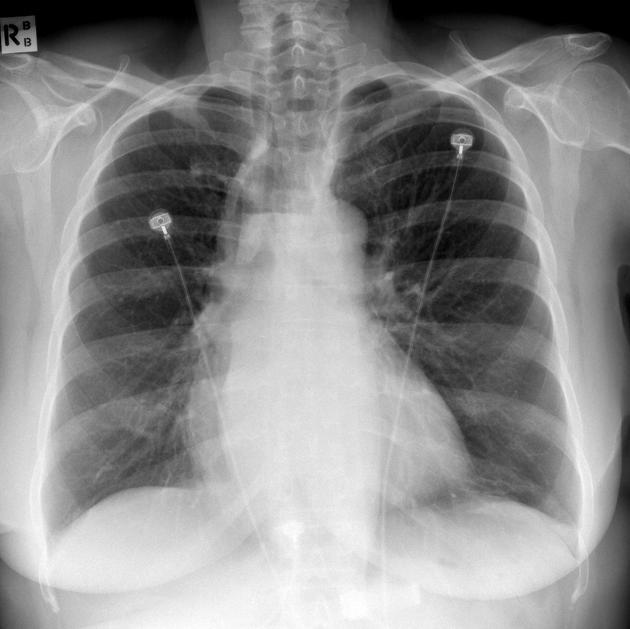

CLINICAL HISTORY:

New cough, ?NG tube position

FINDINGS:

Multiple dense radiopacities demonstrated in both lung bases suggesting aspiration of barium sulphate, I note that a barium swallow was performed yesterday.

Lungs are otherwise clear, no pleural abnormalities.

NG tube is correctly sited, safe for use.

Heart size is normal, hila and mediastinal contours are normal.

IMPRESSION:

Aspiration of barium sulphate

BACKGROUND:

Some patients may aspirate on barium sulphate during GI radiological investigations. If a patient is pre-determined as an aspiration risk then a non-ionic iodinated contrast study is usually performed.